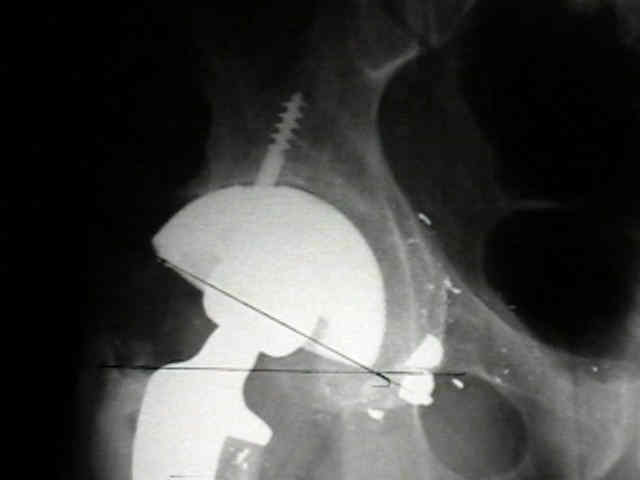

Case Example

- 35-year-old male w/ near anklyosed hip following a GSW to the hip;

- preoperative films appeared to indicate that little or no medialization was necessary;

- postoperative films, however, indicate that the cup was lateralized (hence, reaming was inadequate);

- in retrospect, the radiographs which are rotated externally (like an iliac oblique) tend to falsely minimize the necessary amount of medialization where as X-rays which are rotated internally (like an obturator oblique), tend to over-estimate the necessary amount of medialization